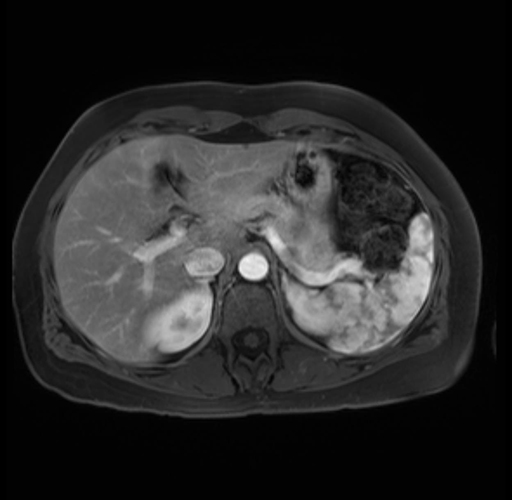

Imaging Analysis

Look through the patient's CT scan to identify any areas of concern for the necessary procedure.

Based on your CT findings, which issue(s) are present and would give reason for "planned slowing down moment(s)" in this case?